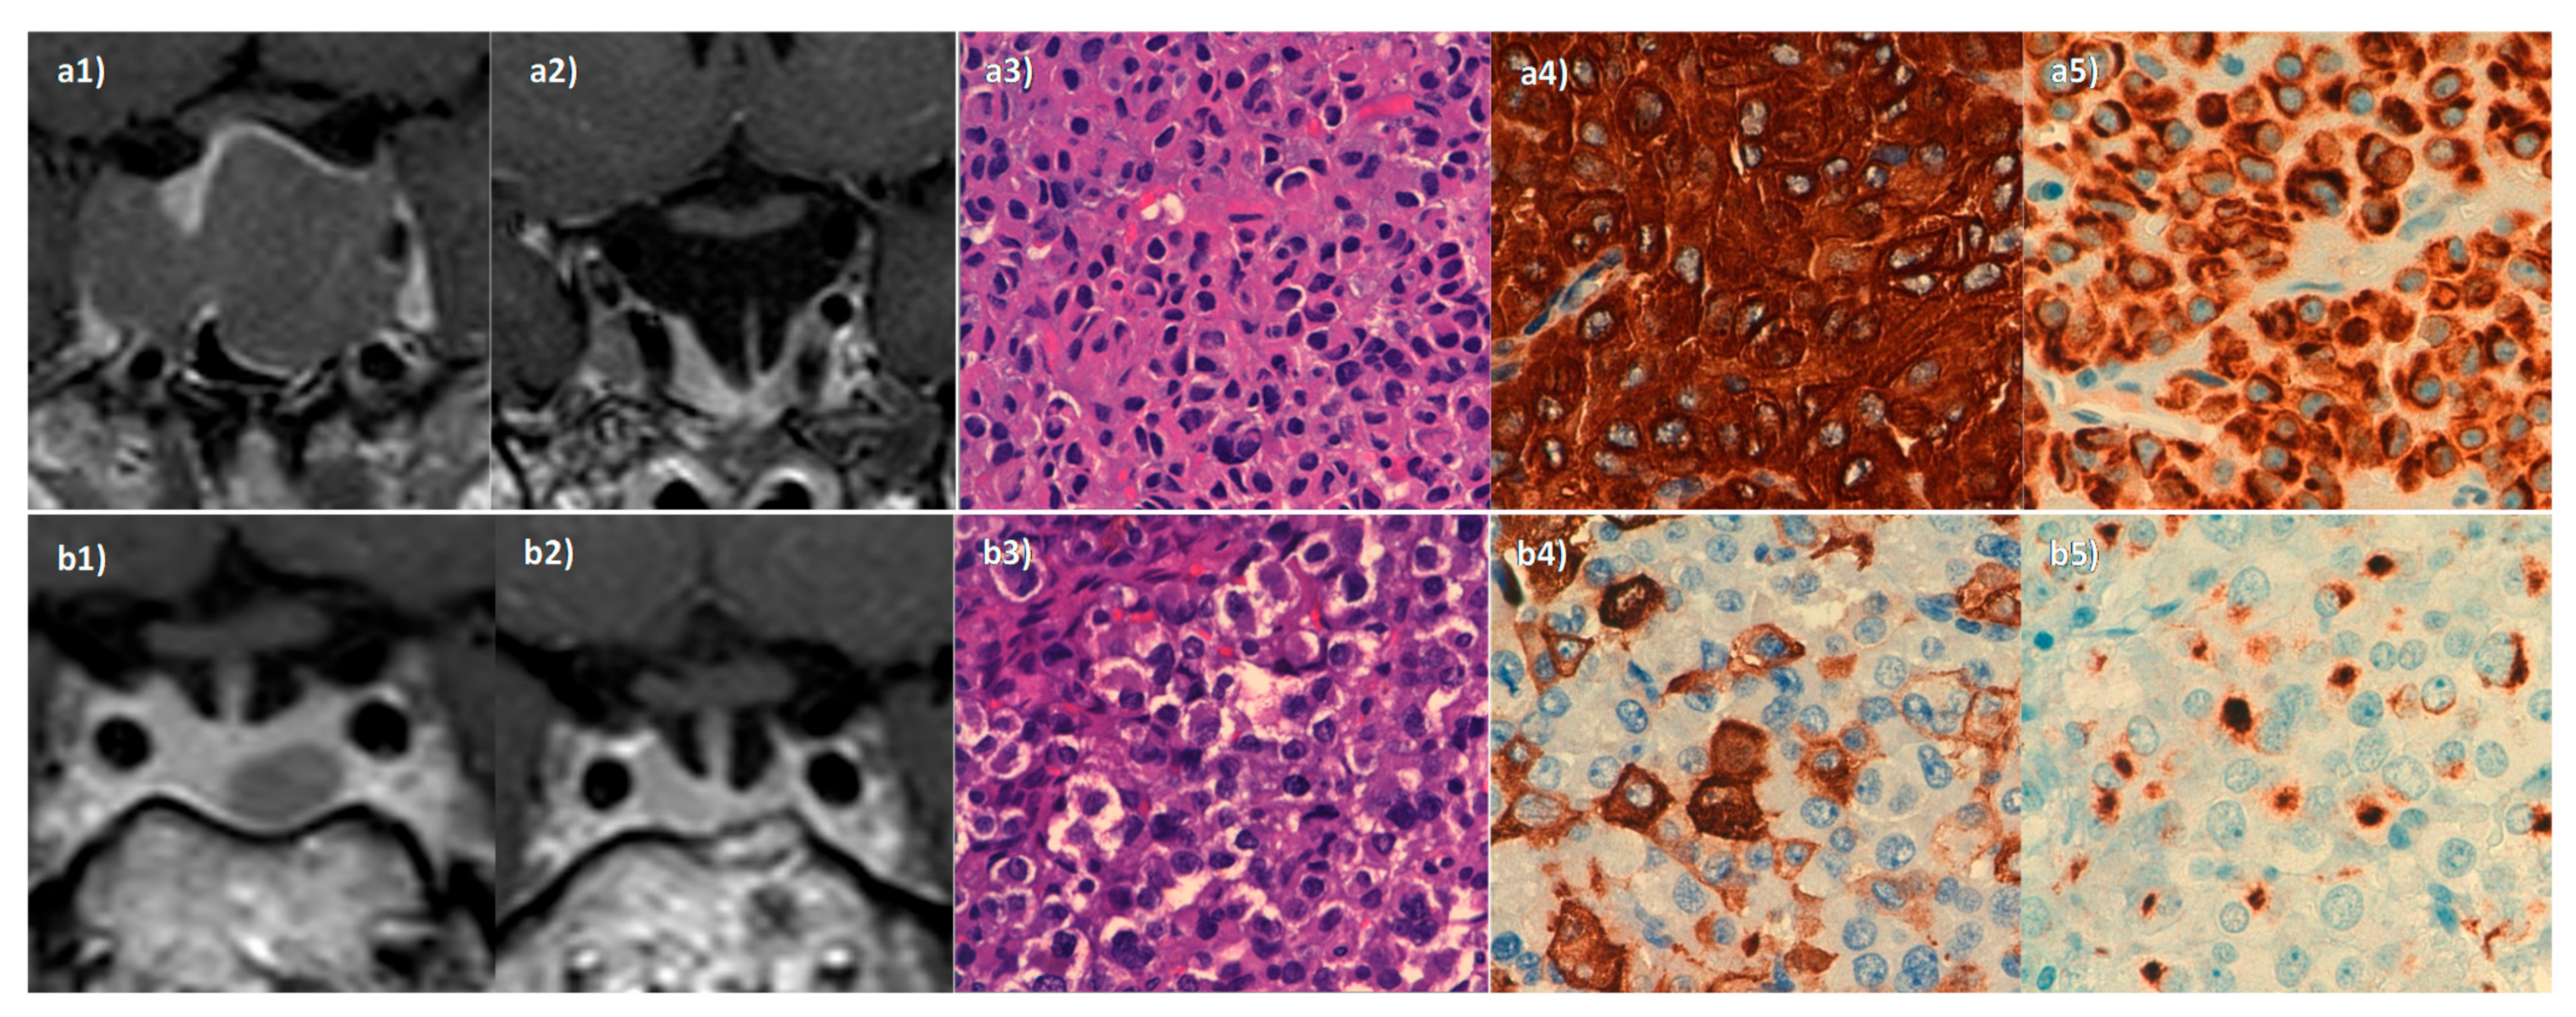

- Araujo-Castro, M.; Pian, H.; Ruz-Caracuel, I.; Cancela, A.A.; Pascual-Corrales, E.; Berrocal, V.R. Presurgical somatostatin receptor ligand treatment does not affect tumor consistency in GH-secreting pituitary macroadenomas. Endocr. Connect. 2021, 10, 102–109. [Google Scholar] [CrossRef]